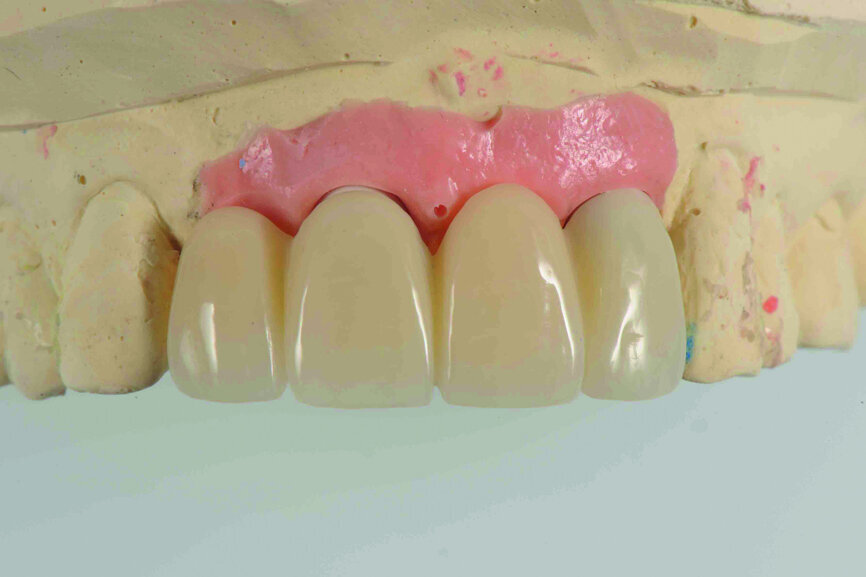

Fig. 13: Reshaping of the artificial gingival contour on the model in order to obtain a good gingival aesthetic effect (performed by dental technician Samuel Chou).

Fig. 14: Provisional restoration on the model.

Teeth #12, 21 and 22 were extracted. Tooth #11 underwent early implantation and tooth #22 immediate implantation with GBR (Figs. 5 & 6). After three months of healing, osseointegration had taken place. An implant level impression was taken for fabricating a provisional bridge supported by temporary abutments for teeth #12–22. The technician modified the shape of the artificial gingiva on the model in order to form the proper gingival curve and emergence profile, then finished the provisional bridge, while the dentist modified the gingival shape using an olive-shaped bur intraorally (Figs. 7–18).

After three months of healing, both hard and soft tissue around the implants had been well maintained, providing a sufficient foundation for the maxillary restoration. In order to form a good gingival shape, either the provisional restoration can be adjusted step by step or the shape of the soft tissue can be designed first, the provisional restoration manufactured to meet the aesthetic demand directly, then the soft tissue intraorally adjusted and reshaped.

In this case, we followed the second option. After using an olive-shaped bur to adjust the form of the gingiva under the pontic, making it match the provisional restoration, which had already been well designed and manufactured, a perfect soft-tissue outcome was achieved.